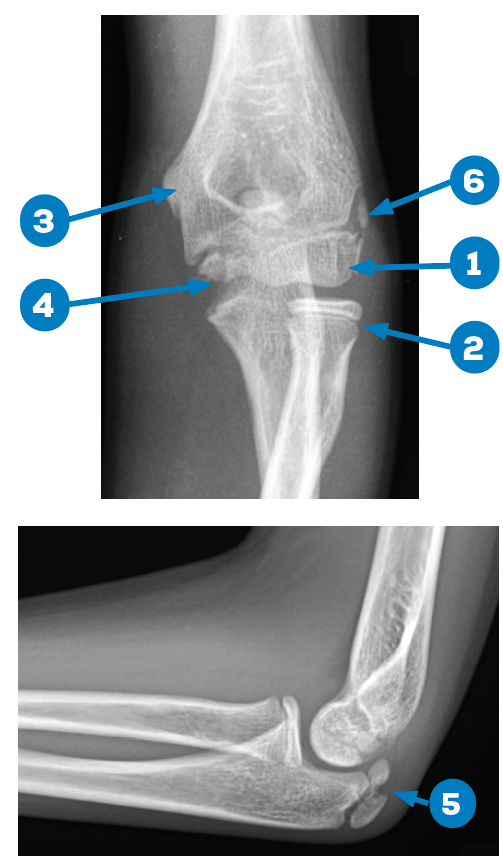

X Ray Elbow

Elbow x-ray - labelling questions | Radiology Case | Radiopaedia.org Anatomy of Elbow X-rays - YouTube Elbow series | Radiology Reference Article | Radiopaedia.org EMRad: Radiologic Approach to the Pediatric Traumatic Elbow X-ray | X Ray Elbow